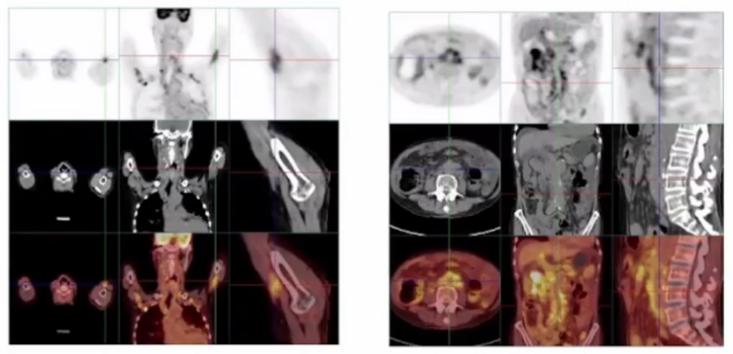

副鼻窦MRI平扫+增强(图1):双筛窦及上颌窦粘膜增厚:右泪腺增大,双腮腺、颌下腺饱满:右中耳乳突炎:颅内肥厚性硬脑膜炎。

图1 副鼻窦MRI平扫+增强PET-CT:

图2 血管PET-CT(1)

图3 血管PET-CT(2)根据PET-CT来看,是不是很像让全身上下到处长肿块的IgG4-RD?病灶累及到了泪腺、胰腺、肺、上述多发血管、升结肠、腹膜、胆管、前列腺、淋巴结等多个器官组织。另外,放射科老师还提示需要结合病理除外淋巴瘤等恶性疾病。